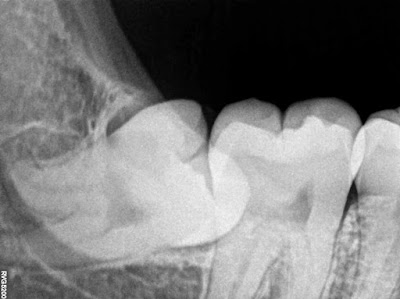

- Bitewing Radiograph

It has been used in Class I&II cases of impacted 3rd molars. It has acurate visualization of relationship between the crown of 3rd molar and the 2nd molar as it is directed with right angle x-ray "0 degree".